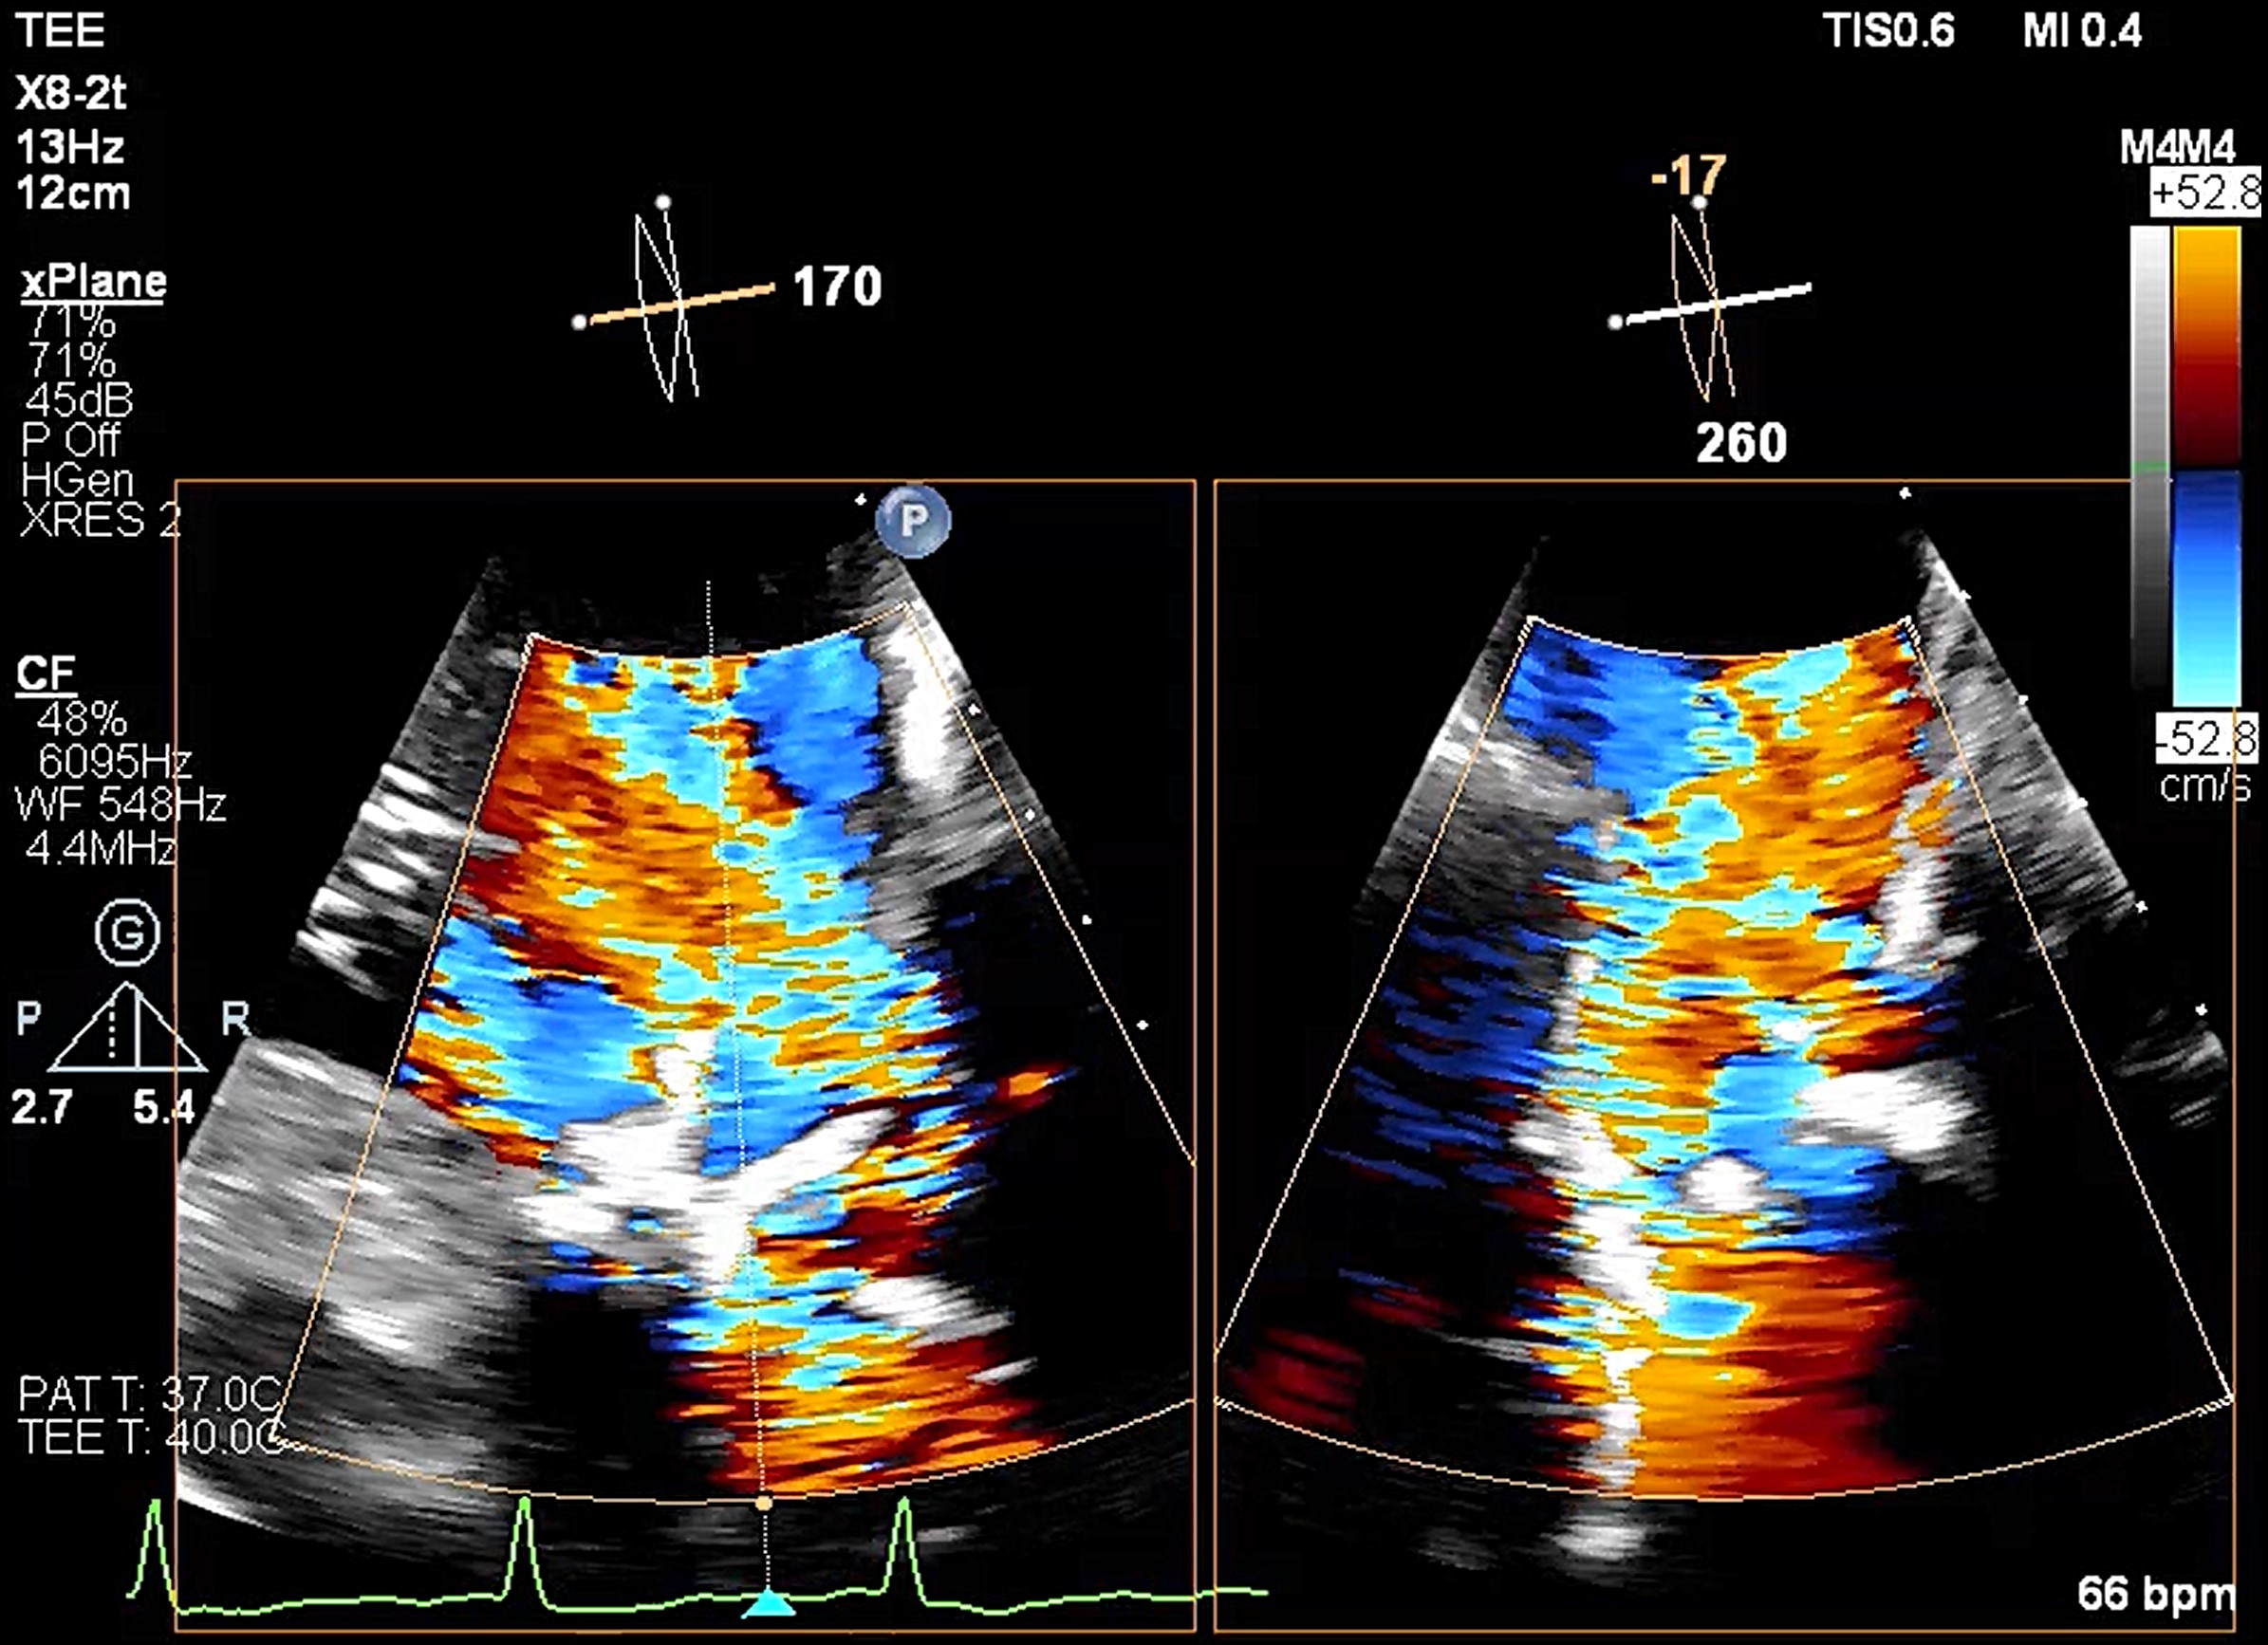

Transesophageal echocardiography revealed severe aortic regurgitation due to THV leaflet perforation following untreated infective endocarditis, along with a preexisting paravalvular leak caused by the calcified raphe of the type 1 bicuspid aortic valve.Given the patient’s deteriorating clinical status despite inotropic support, and after three negative blood cultures and five weeks of antibiotic treatment, the heart team decided to proceed with transcatheter treatment.

A combined procedure including transcatheter closure of paravalvular leak and redo-TAVR, was performed under general anesthesia with transesophageal echocardiographic guidance.1. Bilateral approach via left femoral artery(8Fr non-kinking sheath), right femoral artery(16Fr E-sheath).2. We used a Terumo guide wire accompanied with AL/5F diagnostic catheter to cross the defect of paravalvular leak.3. MP/7F guide catheter accompanied with 6 x 40mm Mustang balloon crossed the paravalvular leak defect by using balloon assisted tracking technique.4. Wire exchanged to Confida super-stiff wire.5. Amplatzer Vascular Plug II 9-12mm occluder was deployed successfully under TEE guidance. 6. TEE showed paravalvular leak downgrade to mild. There was no nearby structure damage, no new pericardial effusion, nor coronary obstruction.7. An Extra-small Safari super-stiff wire was placed in the left ventricle.8. A 23mm Sapien 3 valve was deployed successfully with 1cc overfill.9. The paravalvular leak and valvular AR both sealed successfully, with only minimal paravalvular leak remain.10. The transvalvular mean pressure gradient was 9mmHg, and the valve functioned well.